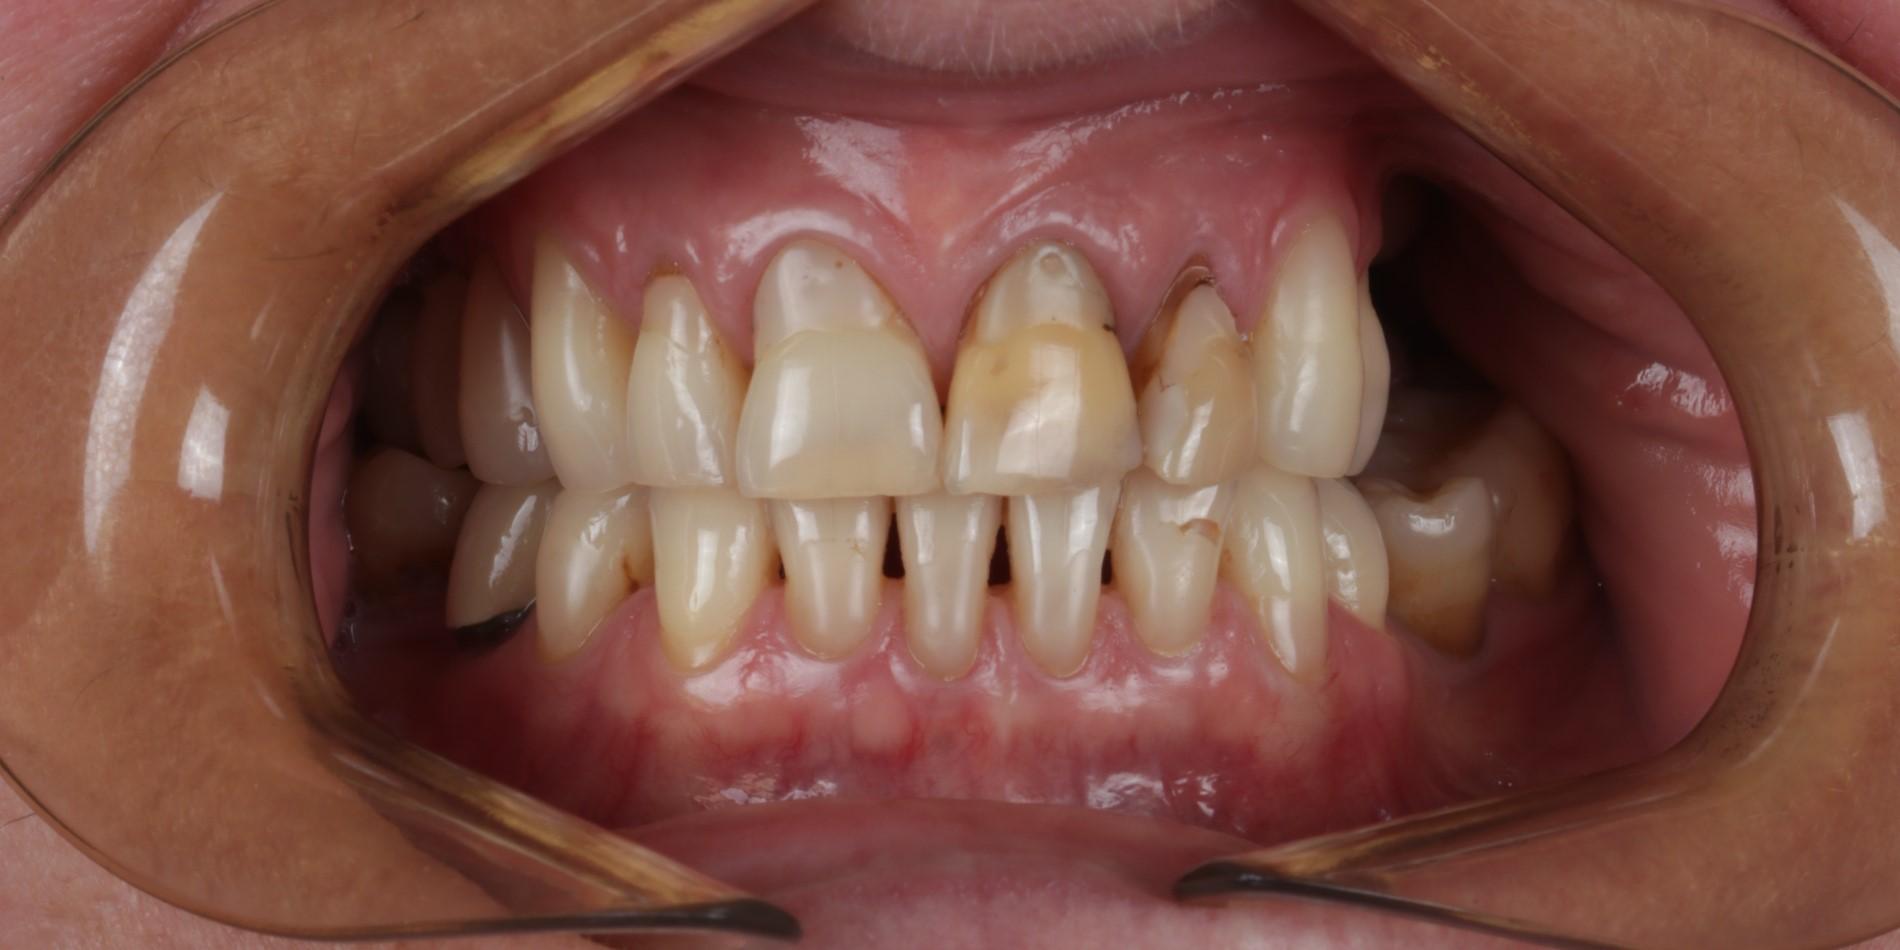

Przedstawiamy metamorfozę naszej Pacjentki, której bardzo zależało na wyprowadzeniu swoich problemów zarówno leczniczo jak i estetycznie.

Pierwszy etap to kompleksowa konsultacja u dr Joanny Zawirskiej-Poły. Podczas tej wizyty zostało wykonane badanie przedmiotowe, podmiotowe, badanie mięśni i stawów, analiza okluzji, badanie stomatologiczne, tomografia komputerowa, rejestracja fotograficzna i długa rozmowa z Pacjentką na temat jej oczekiwań.

Na pierwszej konsultacji Pacjentka dowiedziała się o wszystkich możliwych wariantach działań. Z każdej z przedstawionych opcji zostały również naświetlone wady i zalety danych rozwiązań w perspektywie długofalowej.

Pacjentka, zgłaszając się już na kolejną wizytę świadomie podjęła opcję pośrednią z proponowanych działań: wyleczenie zębów zachowawczo, endodontycznie z zabezpieczeniem protetycznym, estetyczne korekty uśmiechu licówkami, ćwierćkoronami i koronami, jednak bez pełnej przebudowy zwarcia (z zachowaniem starszych odbudów w strefach bocznych, które były wykonane na implantach w przeszłości), która jest zawsze najbardziej polecana, odtwarza prawidłowe kontakty, a także umożliwia lekarzowi i technikowi najlepsze warunki do nadania odpowiednich i harmonijnych kształtów. Te wszystkie działania chronią na przyszłość staw skroniowo-żuchwowy.

Następnie dr Joanna przekierowała Pacjentkę na kompleksowe działania endodontyczne do dr Aleksy Muchy.Po tym dr Joanna mogła przystąpić do działań protetycznych.

Prace protetyczne odbywały się we współpracy z Laboratorium Dental Scan, ściślej z Panią Anną Simierską i Agatą Łatyk-Banasik.